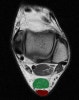

8. Achilles tendon

Axial T1W image assessing the normal Achilles tendon (red). Normally the Achilles tendon is concave or flat on axial imaging.

If it is convex or if it is >6 mm it is abnormal. Incidental accessory soleus muscle (green)